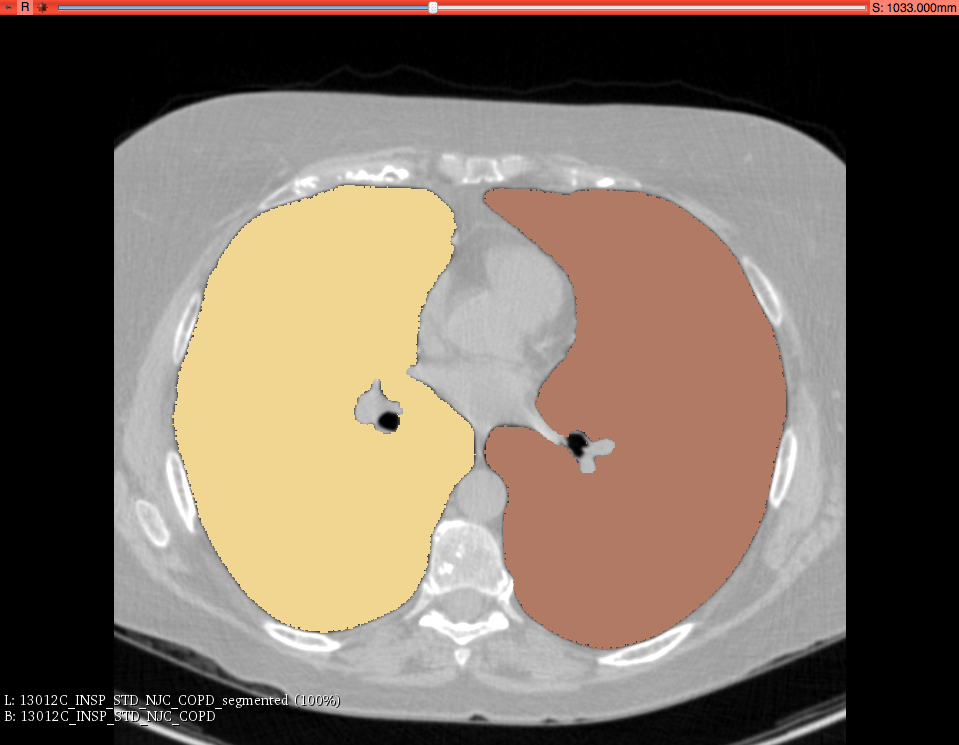

Chest Imaging Platform: segmentation of lungs and pectoralis based on deep learning

Integration of a deep learning infrastructure that supports future integration of deep learning - based tools. Two use cases: lung segmentation and pectoralise segmentation

Illustrations